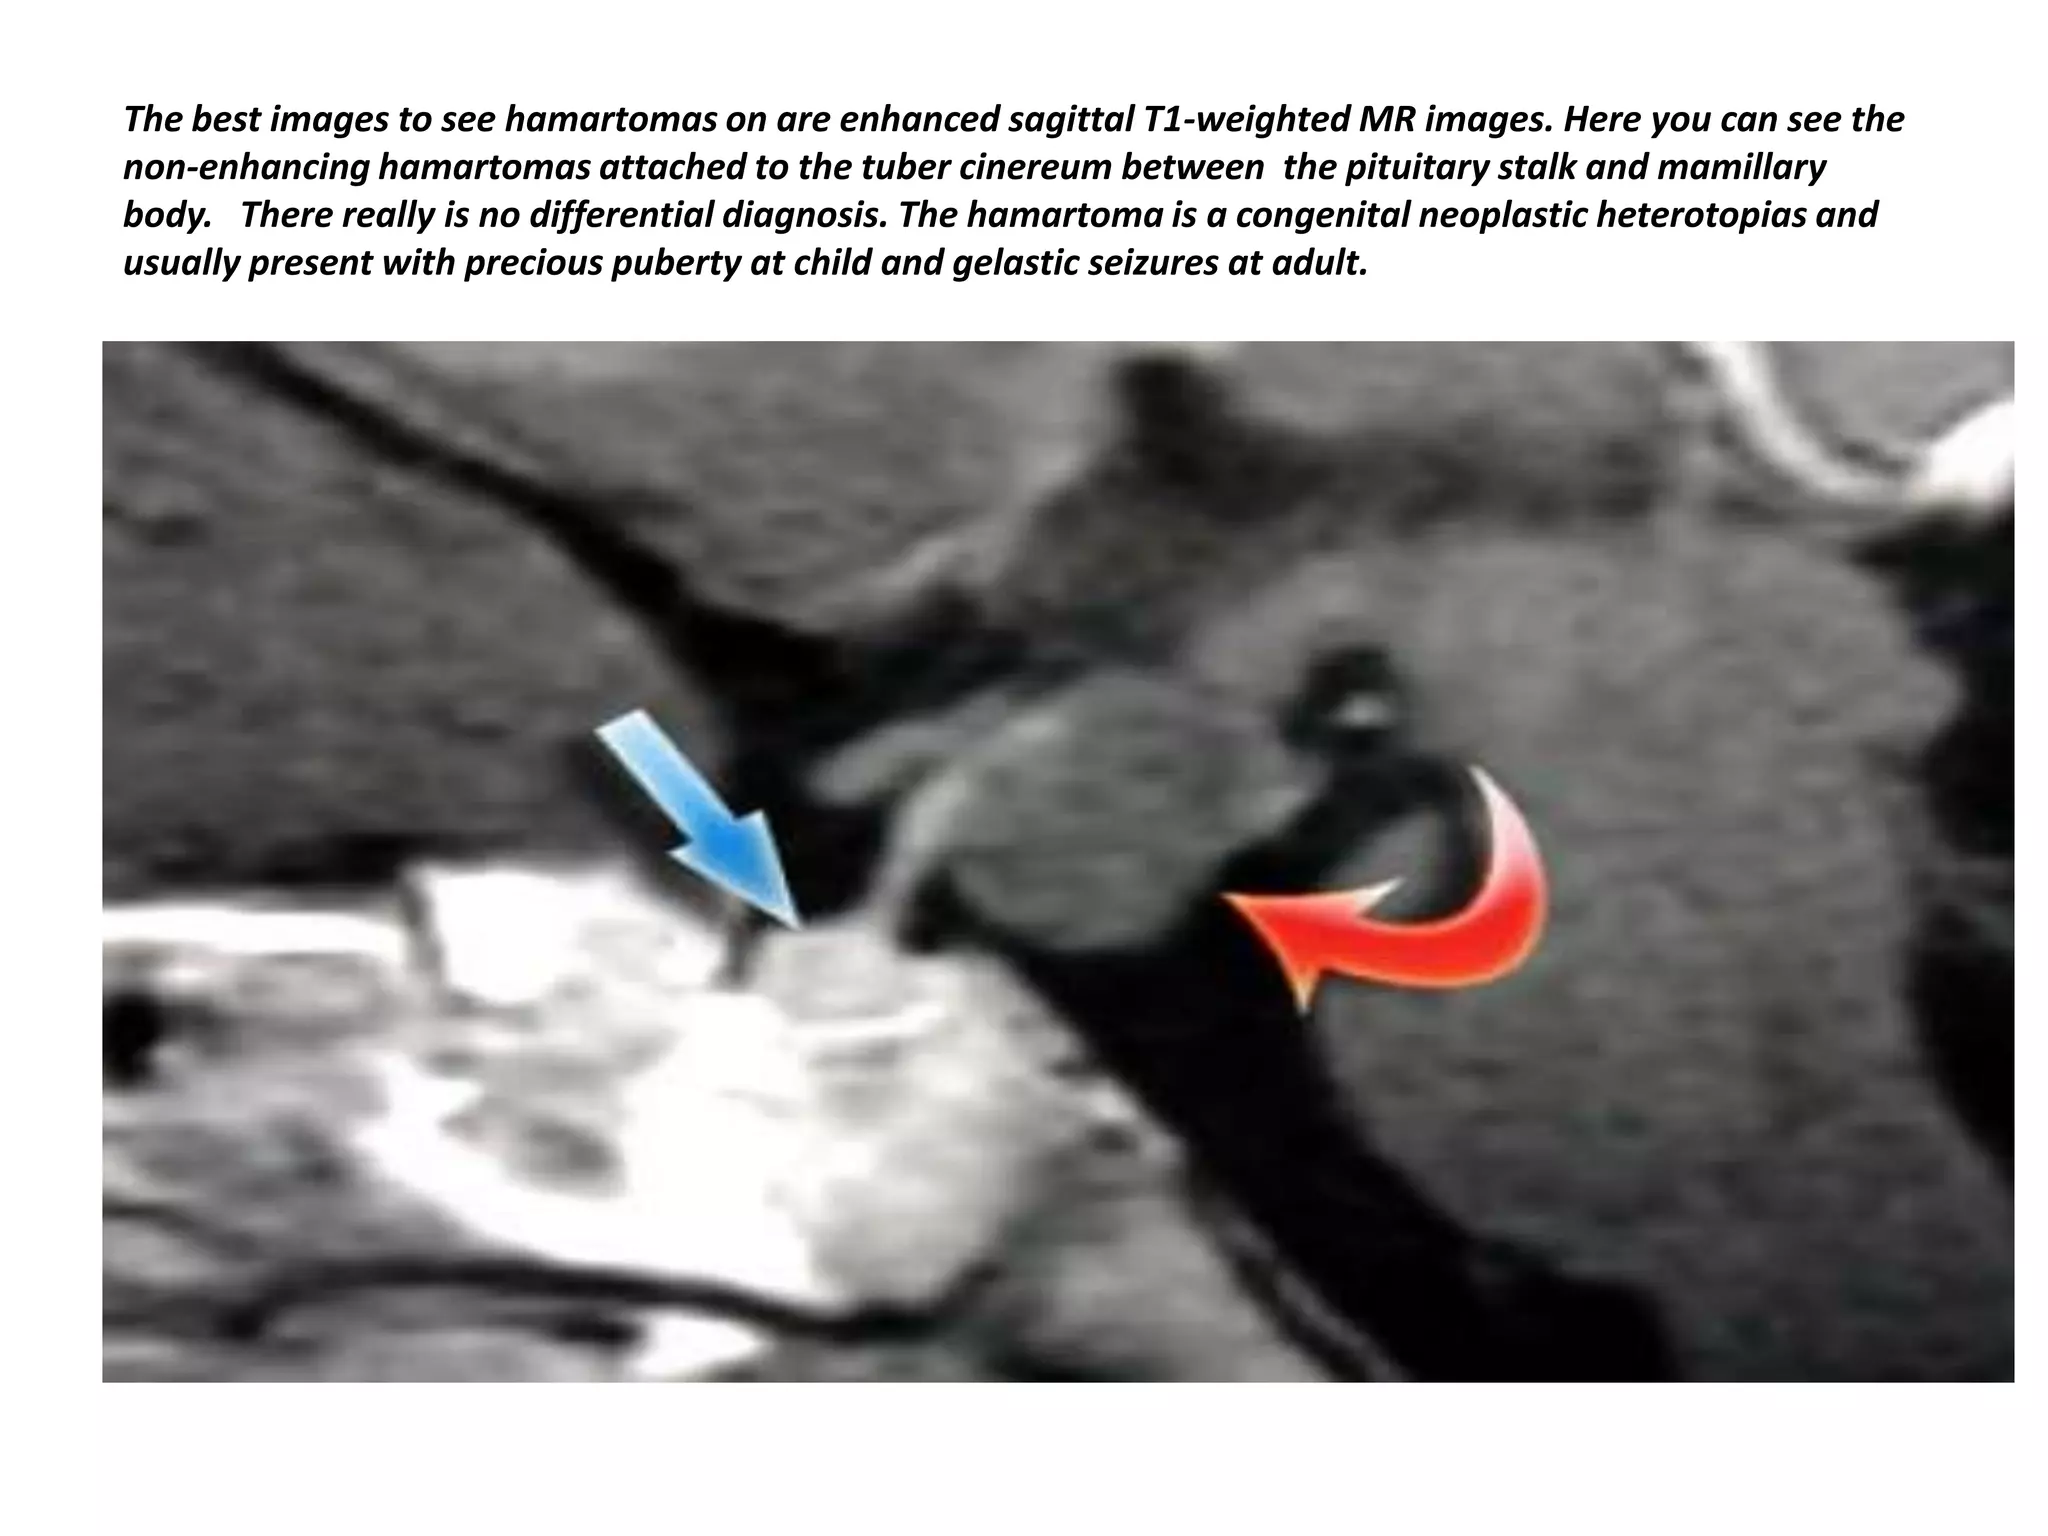

The best images to see hamartomas on are enhanced sagittal T1-weighted MR images. Here you can see the

non-enhancing hamartomas attached to the tuber cinereum between the pituitary stalk and mamillary

body. There really is no differential diagnosis. The hamartoma is a congenital neoplastic heterotopias and

usually present with precious puberty at child and gelastic seizures at adult.